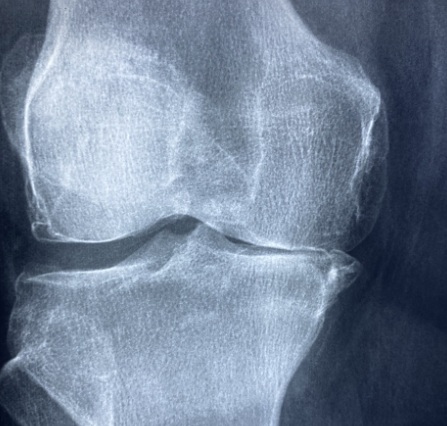

무릎관절염은 관절 내 연골이 점차 닳아 없어지며 염증과 통증을 발생되는 질환입니다. 퇴행성 관절염이 흔하며, 외상성 관절염이나 류마티스 관절염도 무릎에 영향을 줄 수 있습니다. 일반적인 증상은 무릎 통증입니다. 계단을 오르내릴 때, 오래 서 있거나 걸은 뒤에 무릎이 욱신거리며 아프고 뻐근한 느낌이 드는 것이 무릎관절염의 특징입니다. 아침에 일어났을 때 무릎이 뻣뻣하거나, 움직임 시작 시 불편감이 있다면 관절염 초기 신호일 수 있고, 병이 진행되면 통증이 점점 일상생활 속에서도 계속되고, 휴식 중에도 아플 수 있습니다. 연골이 마모되어 관절 간격이 좁아지고, 무릎이 붓거나 열감이 동반하고, 심한 경우 관절 변형과 보행 장애로 이어질 수도 있습니다. 또 무릎에서 '딱딱' 소리가 나거나 관절을 움직일 때 마찰음이 느껴질 수 있고, 관절액이 증가하여 관절 내 물이 차는 증상(관절 삼출)도 관찰됩니다. 증상이 심해질수록 무릎 운동 범위가 줄고, 자연스럽게 근육이 위축되며 활동량도 제한될 수 있습니다.

무릎관절염은 치료 못지않게 관리와 예방이 핵심입니다. 평소 무릎에 무리가 가지 않도록 하고, 꾸준한 운동과 식습관 개선을 통해 관절 건강을 유지해야 합니다. 가장 기본적인 관리법은 무릎에 가해지는 하중을 줄이는 생활습관입니다. 오랫동안 무릎을 굽히는 자세를 피하고, 쪼그려 앉기보다는 의자에 앉는 습관을 들이는 것이 좋으며, 바닥 생활보다 의자와 침대 생활이 관절 부담을 줄이는 데 유리합니다. 체중 관리는 관절 건강 유지의 핵심입니다. 비만은 무릎관절염의 가장 큰 위험 요인 중 하나, 정상 체중을 유지하면 무릎의 마모 속도를 줄일 수 있습니다. 특히 복부비만은 염증 유발 물질인 사이토카인의 분비를 촉진시켜 관절염을 악화시킬 수 있습니다. 운동 습관도 중요합니다. 무릎에 무리가 가지 않는 선에서 꾸준한 운동을 해야 하며, 무릎 주변 근육을 강화하는 스쿼트, 레그 익스텐션, 스트레칭 등은 관절을 지지하는 역할을 합니다. 단, 운동은 과하지 않게 하며 통증이 심할 때는 쉬어야 합니다. 식습관 면에서는 항염증 식단이 권장됩니다. 오메가-3가 풍부한 생선, 항산화 성분이 많은 과일과 채소, 비타민 D와 칼슘이 풍부한 유제품 등이 도움이 됩니다. 인스턴트, 가공식품, 염분이 많은 음식은 자제해야 합니다. 마지막으로, 정기적으로 무릎 상태를 확인하고, 이상 신호가 있을 때는 빠르게 대응하는 것이 중요합니다. 작은 통증이라도 무시하지 말고, 병원에서 엑스레이나 MRI 검사 등을 통해 정확히 진단받는 것이 재발 방지의 시작입니다.